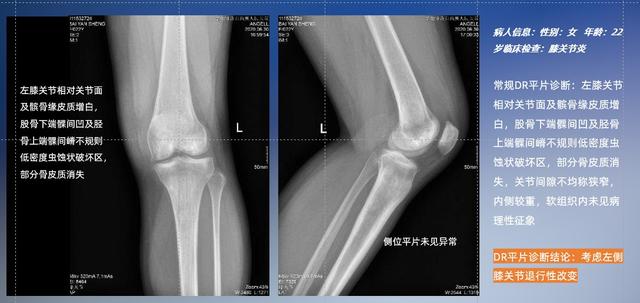

以膝关节疾病检查为例,膝关节在解剖学意义上是一种较为复杂的最大关节,由胫骨上端、股骨下端及髌骨组成。在股骨与胫骨的关节面之间存在两块半月板,分别处于内侧、外侧。膝关节的运动主要为伸、屈,在半屈位时可进行小幅度的旋外、旋内运动。随着现代人们体育生活以及肥胖的增加,膝关节疾病出现高发趋势,特别是关节磨损、膝关节炎与骨关节炎等关节退行性改变,长时间的内翻负荷会造成内侧关节软骨、骨性关节面的磨损。目前针对此类疾病的检查主要为平片下的负重位检查、CT检查以及MRI检查,相较于非负重位检查,负重位检查能更加真实反映膝关节结构中胫骨、股骨、髌骨实际对位关系和关节面的形态特征及关节间隙大小,对膝关节骨关节病诊断准确率高。

普通平片扫描与WR-3D扫描前后诊断结果对比

与此同时,数字化X线摄影技术相较于CTMRI来说,能快速获取真实、直观、满足临床需要的影像。DR的图像具有图像层次丰富、空间分辨力高、影像边缘锐利清晰、密度分辨力高级细微结构表现出色等特点,针对膝关节解剖结构数字化X线摄影技术应用价值很高,尤其是是对骨小梁与骨皮质的显示非常清楚。在负重位状态下,数字化X线三维摄影扫描与重建,能够更好的呈现受检者关节受力改变的状态。ty8天游平台登录科技创新的WR-3D动态三维数字化X线摄影技术,通过数字化X线摄影完成三维扫描并重建三维影像信息,包括MPR多平面重建、MIP重建以及VR绘制。扫描时间短,剂量相较于CT设备大幅缩减,同时成本更低,在临床诊断以及医疗方案制定中具有极大的价值意义。相较于普通平片下的负重位扫描,负重位动态三维扫描摄影技术能够避免二维状态下的组织结构重叠、密度分辨率不足、组织解剖结构难以分辨等问题,WR-3D支持多角度的动态三维摄影观察,能全面的呈现被检查部位在多个角度下三维影像信息,极大的减少了二维负重位检查的漏诊率。